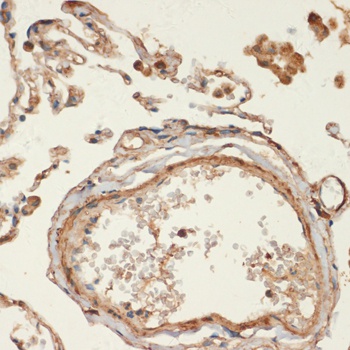

IHC: Formalin-fixed, paraffin-embedded human colon carcinoma stained with SMMHC antibody (MYH11/923).

IHC: Formalin-fixed, paraffin-embedded human Leiomyosarcoma stained with SMMHC antibody (MYH11/923).

IHC: Formalin-fixed, paraffin-embedded human breast carcinoma stained with SMMHC antibody (MYH11/923).

IHC: Formalin-fixed, paraffin-embedded human angiosarcoma stained with SMMHC antibody (MYH11/923).